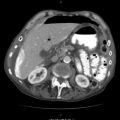

When a urologic injury is suspected in the context of penetrating trauma to the flank, abdomen, or low chest, imaging of the upper urinary system is crucial for diagnosis. CT scan with IV contrast and delayed films at 10 min is the imaging modality of choice for hemodynamically stable patients. CT imaging should permit accurate injury staging based on the AAST criteria, which are highly predictive for operative management. Medial hematoma, with or without extravasation, on early films suggests renal vascular injury while that on delayed films is usually indicative of renal pelvic injury or proximal ureteral injury. Any part of the renal parenchyma that fails to show contrast on early-phase images suggests arterial injury.

Due to improvements in computed tomography imaging and resuscitation methods, operative intervention for renal injuries has been significantly reduced. Currently 36 % of penetrating and less than 5 % of blunt kidney injuries require operative intervention In addition, about 30 % of penetrating and 45 % of blunt grade IV and V injuries are managed nonoperatively. With the broadening criteria for nonoperative management of renal injury, even in penetrating trauma including some gunshots, the only absolute indications for operative management are hemodynamic instability, expanding or pulsatile perirenal hematoma, incomplete renal injury staging, renal pelvic injury, or non-visualization of the injured kidney on IVP. AAST stage I–III renal injuries are usually hemodynamically stable and are managed nonoperatively. Isolated stage IV renal injuries may be managed nonoperatively when hemodynamically stable but must be continually reassessed and re-imaged by CT scan at 48 h or sooner if there is clinical decompensation. Superselective embolization may be attempted for certain patients with stage IV renal injuries who fail conservative management due to persistent bleeding from segmental arteries. Stage V renal injuries nearly always require operative intervention. With these guidelines in mind however, renal injuries suffered from penetrating trauma are almost always associated with other injuries that dictate the decision to operate.